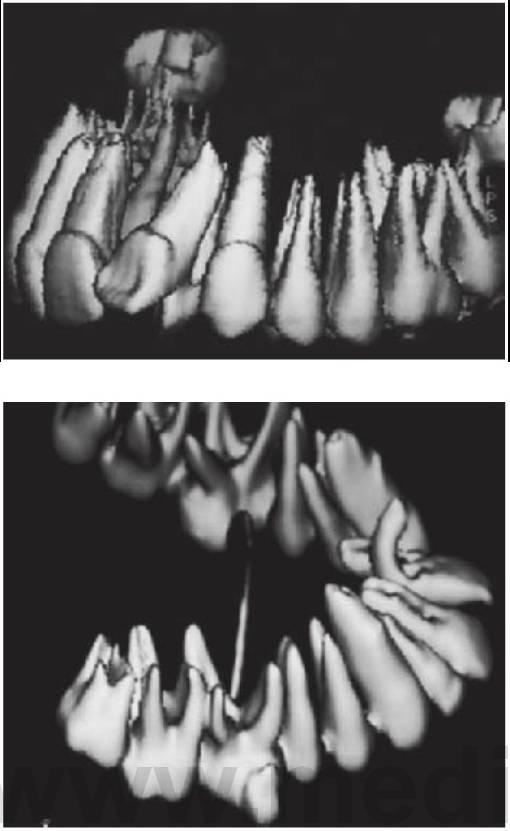

- Los dientes tuberculados o cónicos invertidos requieren extracción quirúrgica (fig. 9.8D) tan pronto como sea posible para permitir la erupción sin obstáculos del diente permanente.

- Resulta esencial localizar la posición del diente que debe extraerse antes de la cirugía. Pueden realizarse radiografías periapicales que emplean la técnica del desplazamiento del tubo (tube-shift) para localizar el diente, pero siempre entrañan la posibilidad de errores e interpretaciones erróneas. De la misma manera, pueden utilizarse radiografías panorámicas y oclusales maxilares estándar. La proyección oclusal de vértice permite obtener una muestra más precisa de la localización horizontal y anteroposterior, por lo que es la preferida (fig. 9.8C) para ayudar a determinar el procedimiento quirúrgico óptimo. Algunos centros prefieren no utilizar esta vía debido a una excesiva radiación en el cráneo.

- Las técnicas digitales de imagen que utilizan tomografías de haz cónico proporcionan una buena definición e imágenes tridimensionales de la cabeza y el cuello y emiten mucha menos radiación que la tomografía computarizada tradicional (TC) (v. fig. 9.18 más adelante).